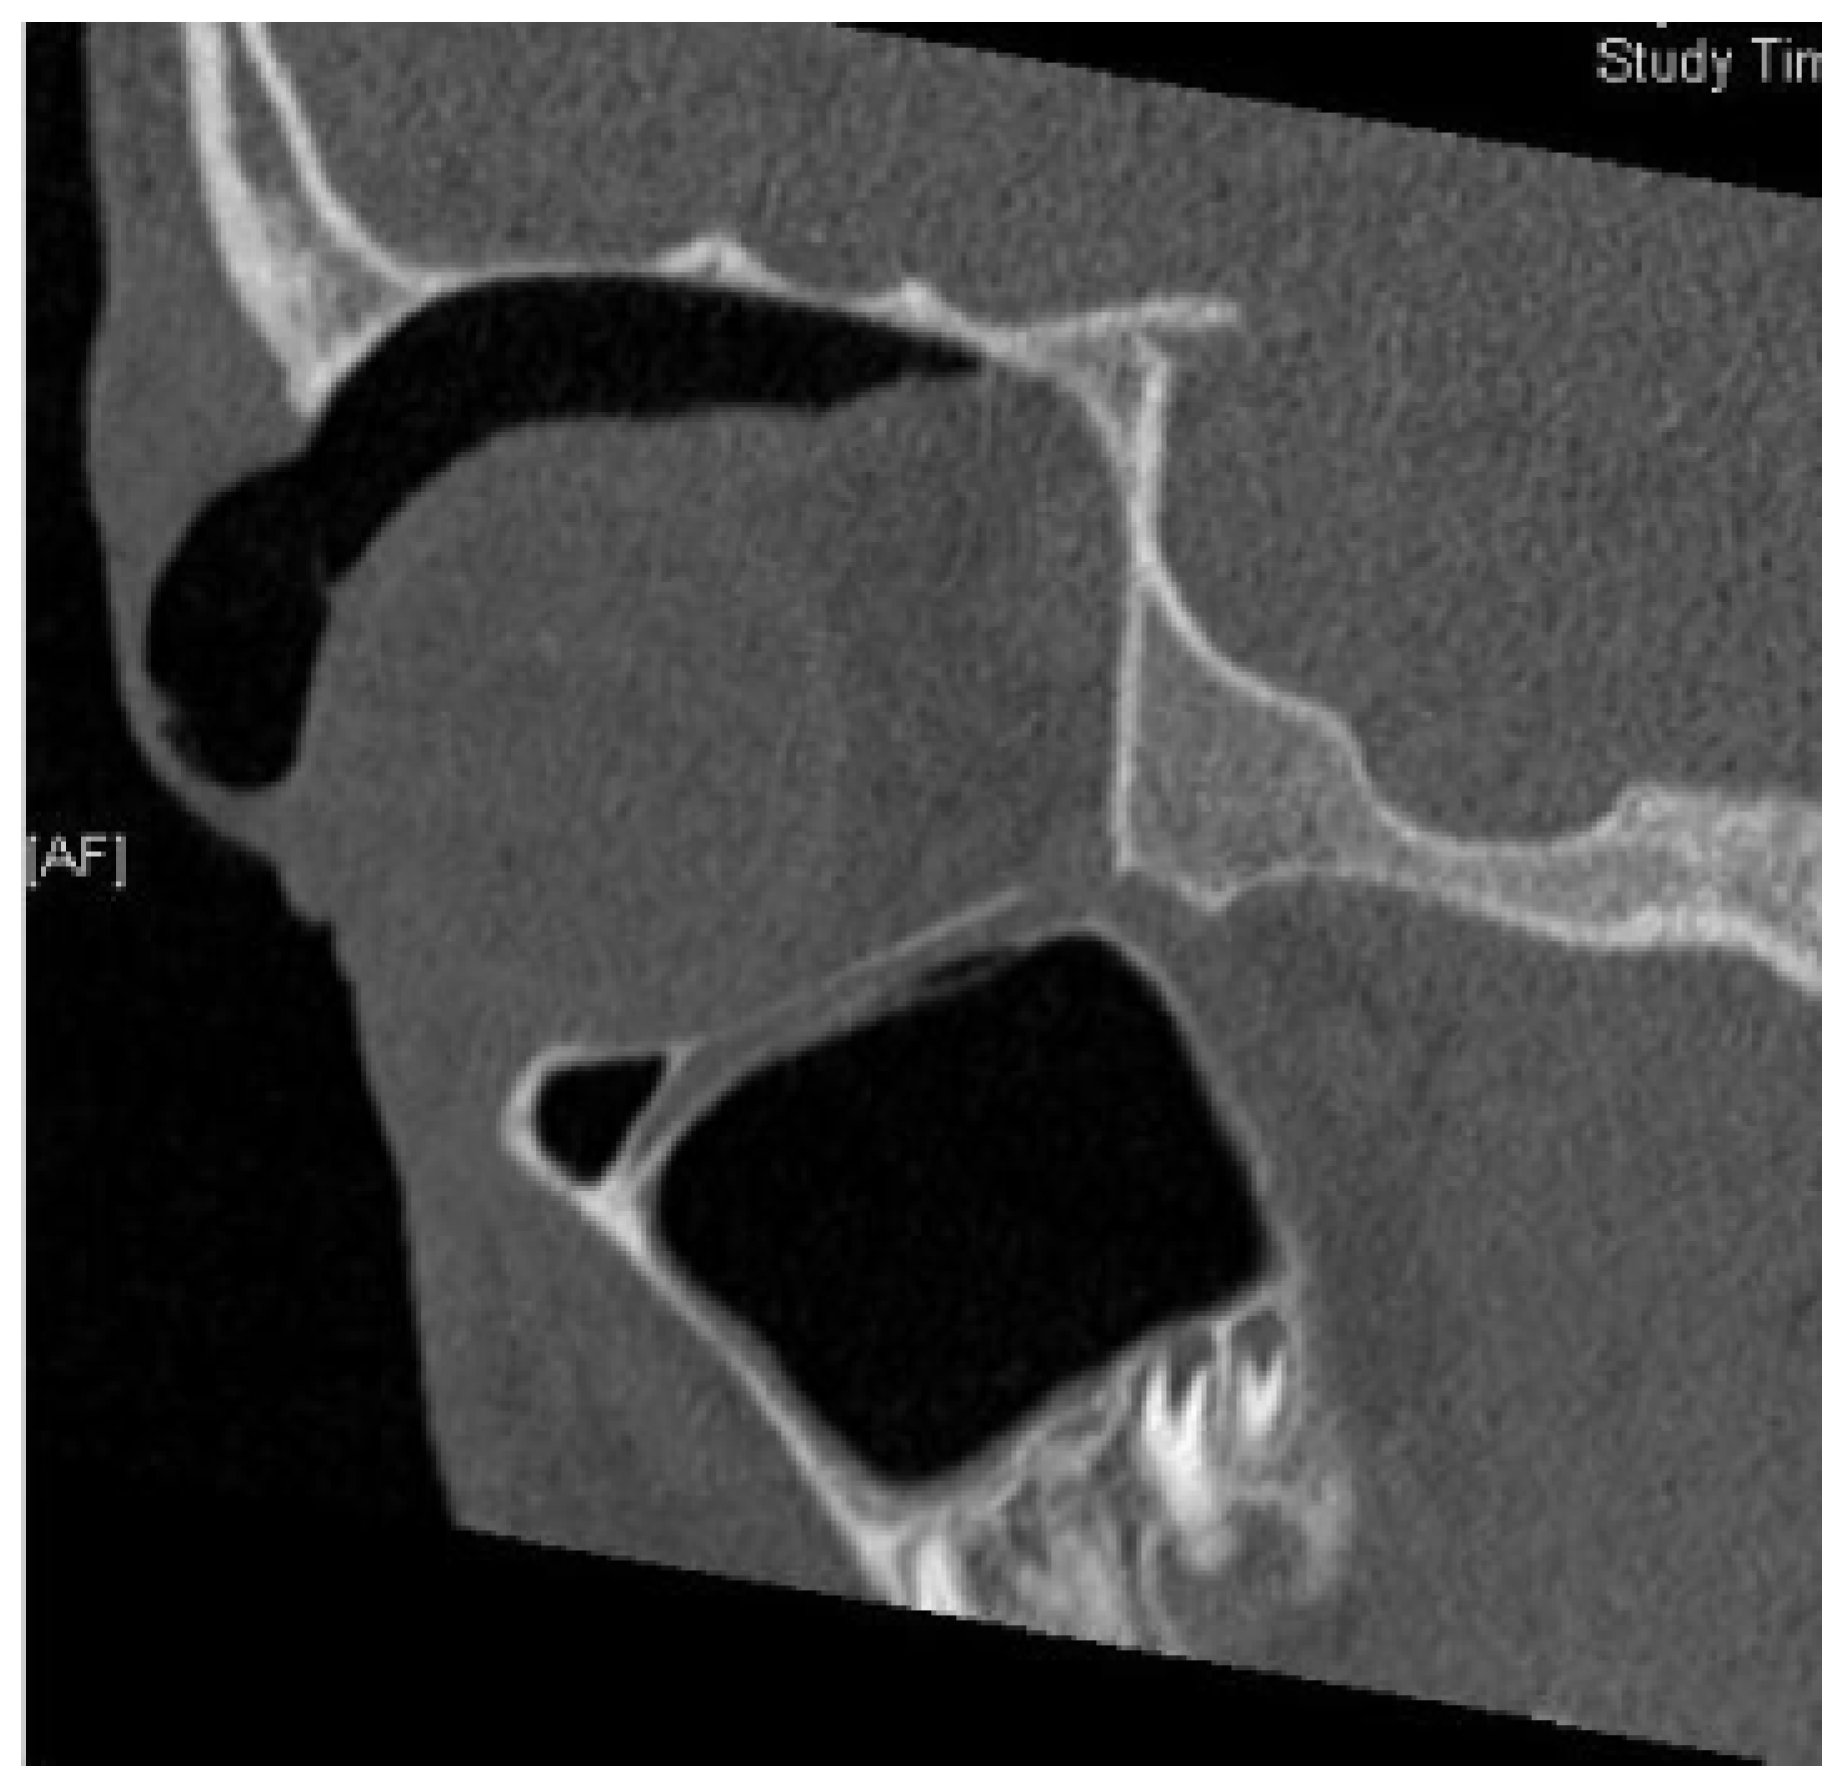

Medial Wall Fracture and Orbital Emphysema Mimicking Inferior Rectus Entrapment in a Child

:Case Report